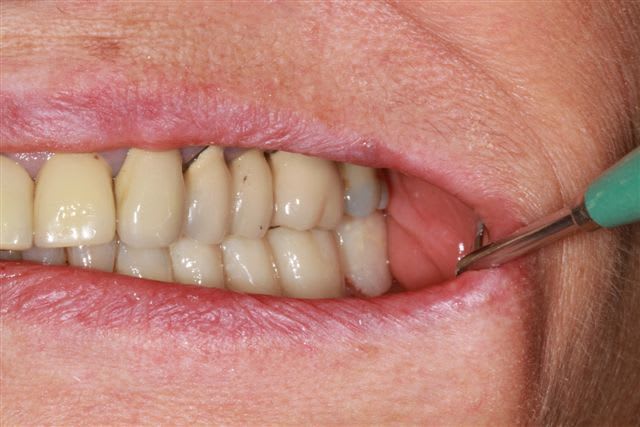

ce matin, grosse séance (4 h), pour le bas dépose des couronnes retraitement, taille et provisoires pour secteur 3 et 4 d'après le waxup, puis équilibration (le haut ne correspond pas encore), et bien désolé de te décevoir enlaye, mais les waxups donnent un résultat tip top...

secteur 3 et 4 ça avance,avec mes options pour l'occlusion, fonction du haut "chancelant", une fois le haut "stabilisé", je modifierais sans doute le bas.